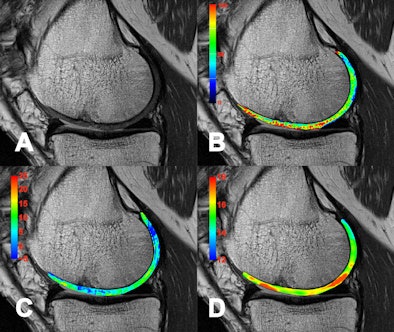

| A collection of images in a patient eight years after autologous osteochondral transplantation. Besides a standard morphological image (A) which shows minor defects in the transplantation area, several compositional (biochemical) MR methods are presented. T2 mapping (B) is collagen and water-specific, while chemical exchange saturation transfer (CEST) (C) and sodium imaging (D) are proteoglycan-specific MR methods. All biochemical methods reveal alterations in the normal structure of the cartilage transplant. So far CEST and Sodium (23Na) imaging can only be performed with 7-tesla MR scanners. |

High-field MR systems at 7.0 tesla with their higher signal-to-noise ratio (SNR) also make nuclei other than protein, such as sodium (23Na), phosphorus (31P), carbon (13C), and others, visible. This is especially the case for sodium imaging, due to its rather low sensitivity, which is limited at 3.0 tesla and below, and it has proven to be very valuable in the aftercare of cartilage repair surgery. Sodium imaging correlates with the proteoglycan content of cartilage, which is a significant measure of tissue quality due to its important role in the biomechanical functions of the cartilage. Higher SNR and spectral resolution at 7.0 tesla are also responsible for a significant improvement in phosphorus spectroscopy, which allows for quantification of the energy metabolism of muscle in significantly reduced examination times in comparison with 3.0 tesla, making it a highly attractive application to be introduced to clinical use.